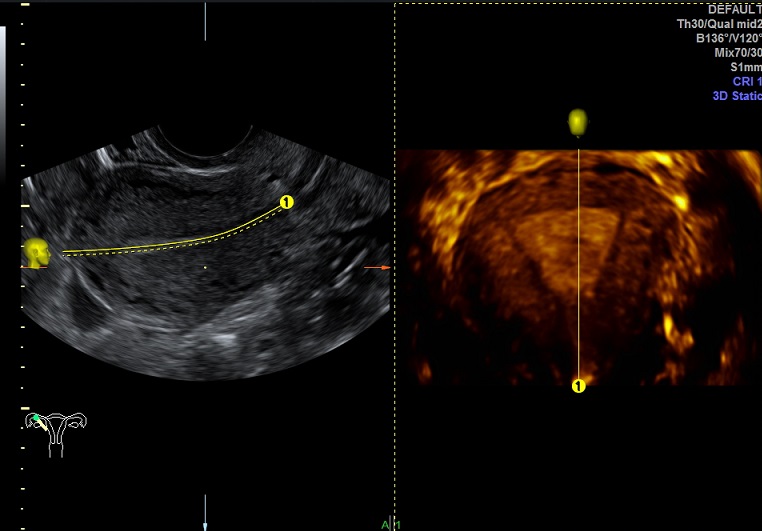

| 女性,25岁,继发性不孕1年余,难免流产4次。 | ||

2015-3-23 月经第19天检查 |

2015-3-23图示